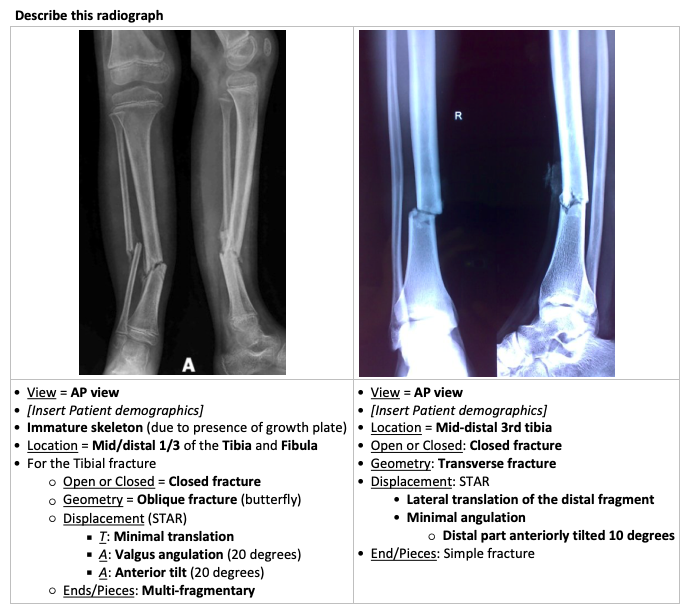

Describe this radiograph